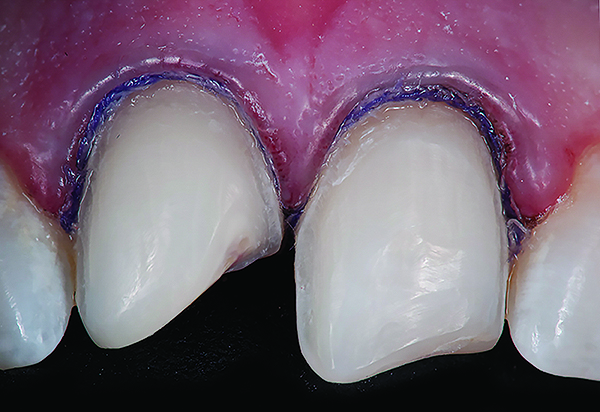

Fig 1. Preoperative (Fig 1), preparation (Fig 2), and final postoperative (Fig 3) images of a two-unit CL-I feldspathic veneer case.

Figure 1

Fig 2. Preoperative (Fig 1), preparation (Fig 2), and final postoperative (Fig 3) images of a two-unit CL-I feldspathic veneer case.

Figure 2

Fig 3. Preoperative (Fig 1), preparation (Fig 2), and final postoperative (Fig 3) images of a two-unit CL-I feldspathic veneer case.

Figure 3